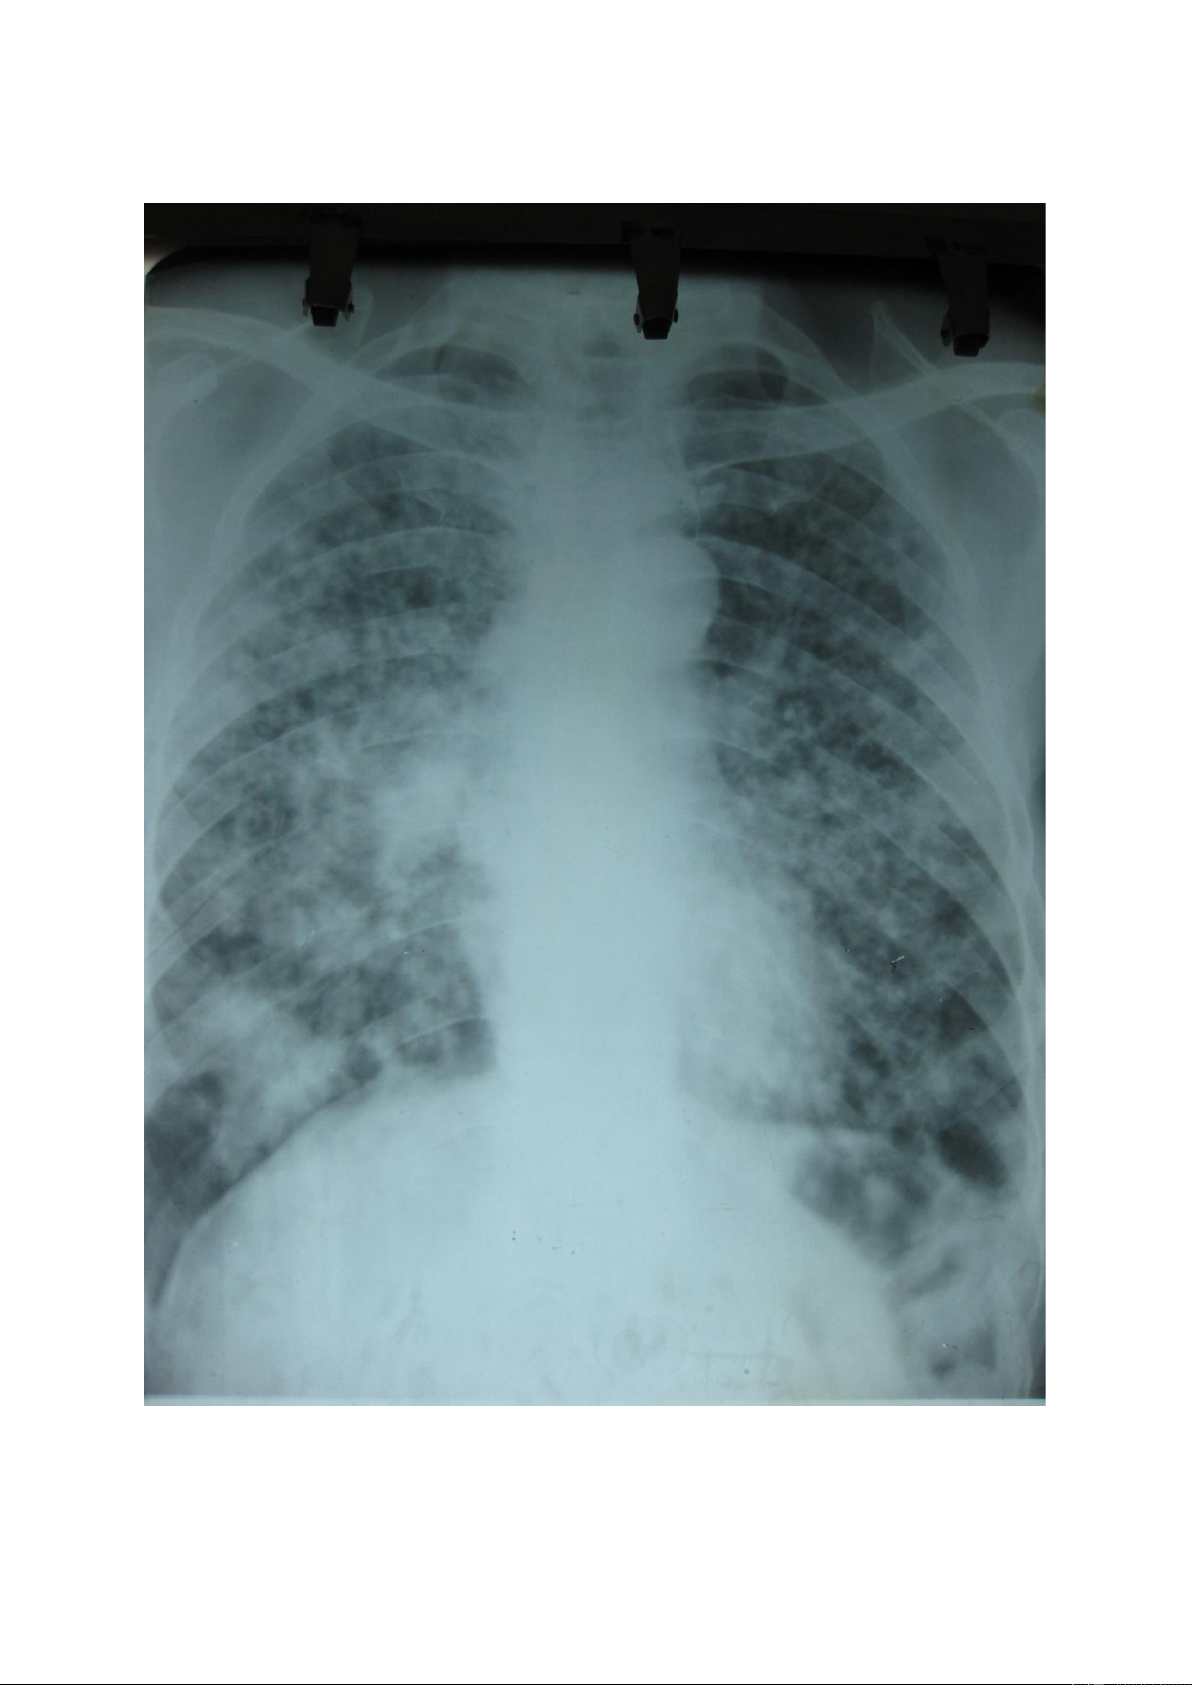

Nốt mờ lớn: là tổn thương có kích thước >3mm và < 3cm, số lượng có thể đơn

độc hoặc nhiều, kích thước có thể đều hoặc không đều, đậm độ cản quang khác nhau. lOMoAR cPSD| 22014077 lOMoAR cPSD| 22014077 1.3.